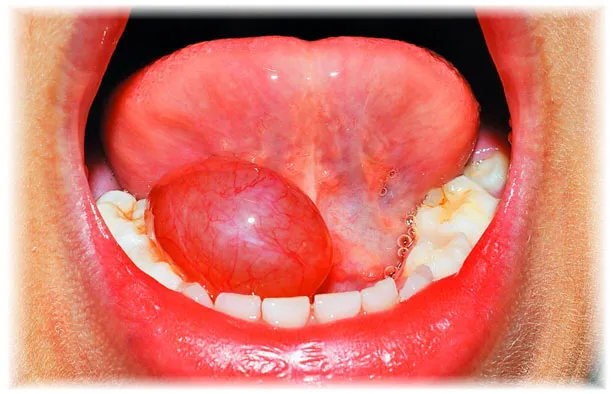

Torbiel ślinianki przyusznej może manifestować się w różnorodny sposób, a jej objawy są kluczowe dla zrozumienia tego schorzenia. Najczęściej występującym objawem jest niebolesny, niebieskawy obrzęk w okolicy wargi dolnej, powierzchni brzusznej języka lub błony śluzowej policzka. Taki obrzęk może być wynikiem blokady przewodu wyprowadzającego ślinę, co prowadzi do zahamowania przepływu śliny. W efekcie, średnica przewodu może się zwiększać, co przypomina torbiel. Zmiany te mogą być także spowodowane przez drażnienie tkanek, co prowadzi do stanów zapalnych.

Warto zauważyć, że rozmiar obrzęku może ulegać zmianom w zależności od produkcji śliny oraz ewentualnego drenażu. U niektórych pacjentów, objawy mogą być łagodne i nieprzeszkadzające w codziennym życiu, podczas gdy u innych mogą prowadzić do bólu i dyskomfortu. W przypadku ludzi, torbiel ślinianki przyusznej często jest związana z zaburzeniami przepływu śliny, co może być wynikiem różnych czynników, takich jak zmiany zapalne lub nowotworowe. Zrozumienie tych objawów jest kluczowe dla podjęcia odpowiednich działań terapeutycznych.